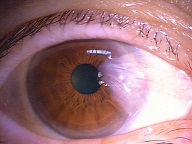

今日いらした24歳女性の症例です。

強い充血を認めます。写真の右側は、はやり目に特徴的な後遺症で、黒目(角膜)が濁っている写真です。もう少し分かりやすい、ヒドイ症例の写真を出したいのですが、ヒドイ症例は第一診察室には入らないようにしていただいたり、写真をとるなどの、余分な時間を少しでも省いて診療を行い、院内感染を予防する必要があり、なかなか難しいのです。